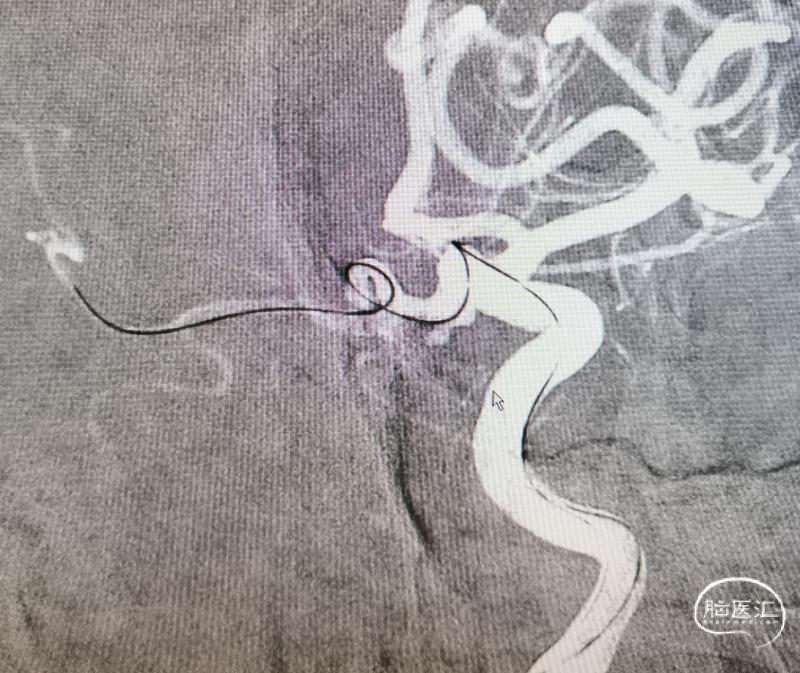

三米交换导丝,顺利到位。就看支架导管得了。既往有过顶破的经历,因此特别小心。好在三米支撑导丝的支撑能力比较好。但是也是一点一点的调整支架导管的位置,好在一切努力没有白费,支架导管一点一点越过后交通动脉起始,慢慢爬过过度弯曲之处。好在导管还能前行一些,紧绷的心终于放下了。起码离成功还有一半。于是就是弹簧圈微导管的到位,塑了个“猪尾”,第一次角度稍微大了一点点。如图。到位还算容易。也没有想太多,直接就用最小的圈,先把瘤填上,防止再次出血,可是现实并没有那么容易。

第一次